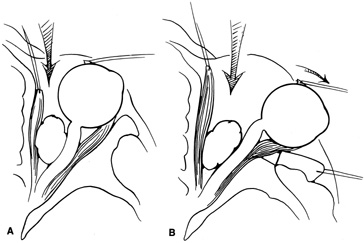

Fig. 11. A. Lateral canthotomy incision is made with straight iris scissors. B. Periosteum is elevated off of the lateral orbital rim. C. Wide undermining allows retraction of the skin incision to permit superior

and inferior osteotomies to be made with the air-driven saw. D. The bony rim has been outfractured. Because of the distensibility of the

skin, it is possible to remove a large bone flap through the small

canthotomy incision. E. The intraconal mass is extracted with the aid of the cryoprobe. F. The bone fragment is positioned for resuturing.

Fig. 11. A. Lateral canthotomy incision is made with straight iris scissors. B. Periosteum is elevated off of the lateral orbital rim. C. Wide undermining allows retraction of the skin incision to permit superior

and inferior osteotomies to be made with the air-driven saw. D. The bony rim has been outfractured. Because of the distensibility of the

skin, it is possible to remove a large bone flap through the small

canthotomy incision. E. The intraconal mass is extracted with the aid of the cryoprobe. F. The bone fragment is positioned for resuturing.

|